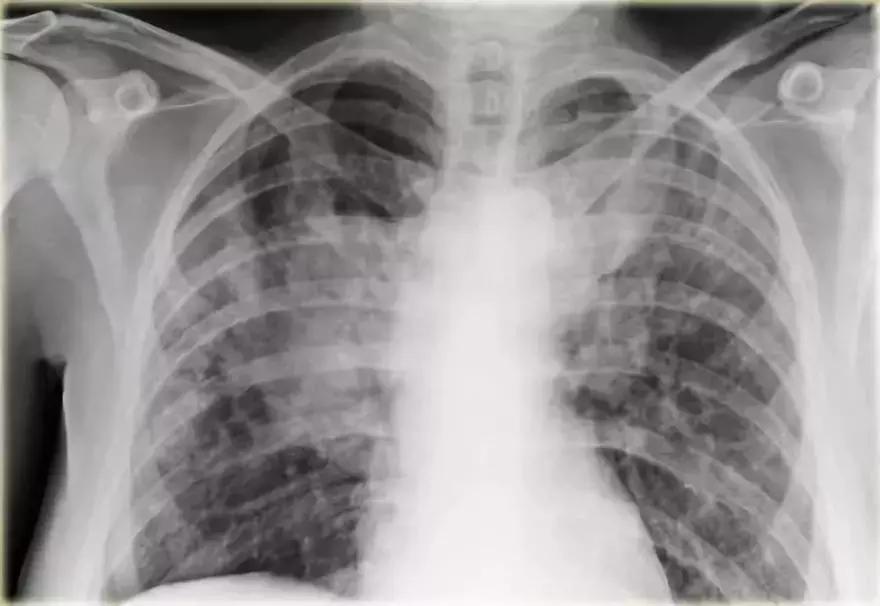

支气管肺炎弥漫性实变

➢ 患者患有高烧咳嗽,诊断为弥漫性支气管炎。

➢ 与始于肺泡的大叶性肺炎不同,支气管肺炎作为急性支气管炎始于气道。

➢ 多发模糊阴影,进展期能产生弥漫性实变,病变不能越过叶间裂,但通常在多个肺段发生。

➢ 支气管肺炎可由多种微生物引起

诊断结果:军团菌肺炎

图11 支气管肺炎弥漫性实变